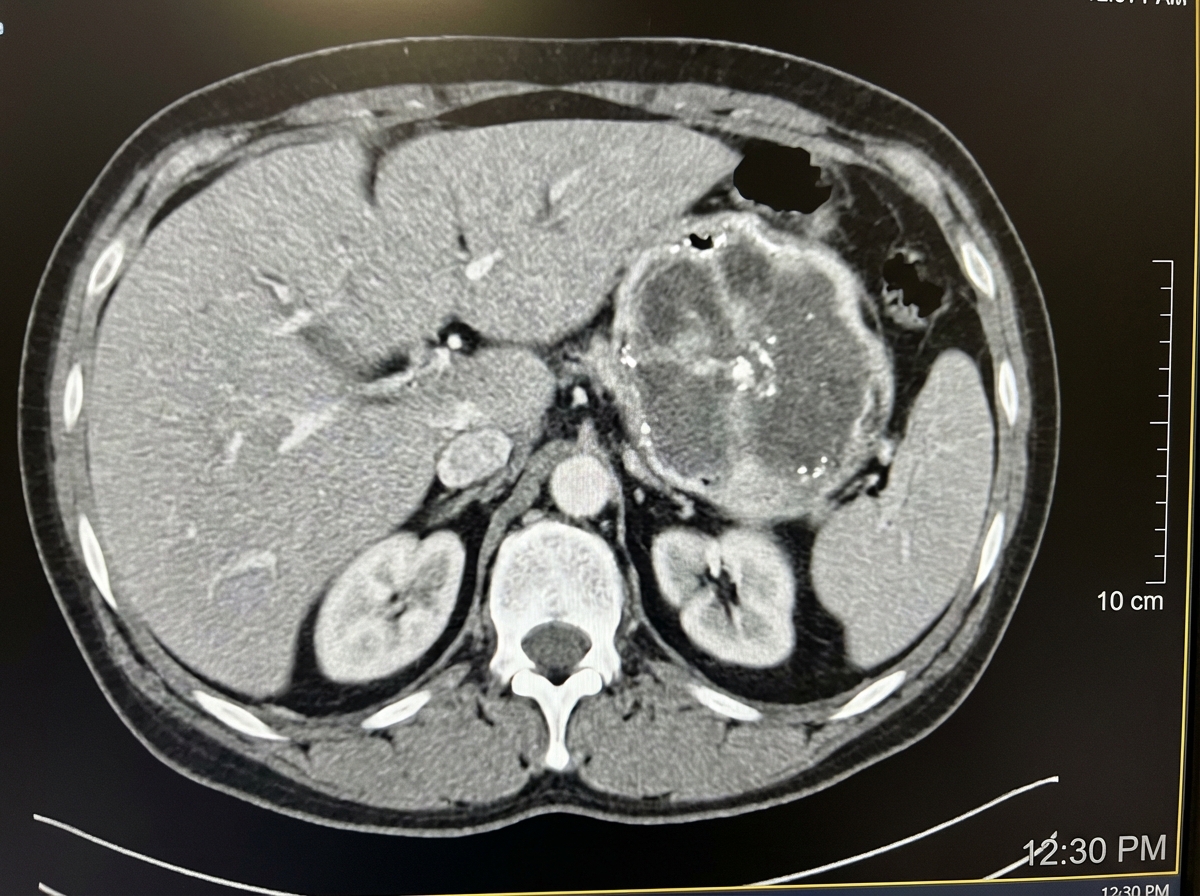

A 40-year-old patient presents with episodic hypertension, severe headache, diaphoresis, and palpitations. The CT scan of the abdomen is shown in the image. What is the most likely diagnosis?

Explanation: ***Pheochromocytoma*** - The classic triad of **episodic hypertension**, **severe headache**, **diaphoresis**, and **palpitations** strongly suggests **catecholamine excess** from a pheochromocytoma. - CT imaging typically shows an **adrenal mass** with **heterogeneous enhancement** and possible **central necrosis**, confirmed by elevated **24-hour urine metanephrines** or **plasma metanephrines**. *Coarctation of the aorta* - Presents with **continuous hypertension** and **blood pressure differential** between upper and lower extremities, not episodic symptoms. - Associated with **rib notching** on chest X-ray and **weak femoral pulses**, which are absent in this case. *Primary hyperaldosteronism* - Causes **sustained hypertension** with **hypokalemia** and **metabolic alkalosis**, not episodic catecholamine symptoms. - Presents with **muscle weakness** and **polyuria** due to **aldosterone excess**, lacking the classic triad described. *Renal artery stenosis* - Results in **renovascular hypertension** with **renal bruit** and possible **flash pulmonary edema**, not episodic symptoms. - Associated with **atherosclerotic disease** or **fibromuscular dysplasia**, typically showing **kidney size asymmetry** on imaging.